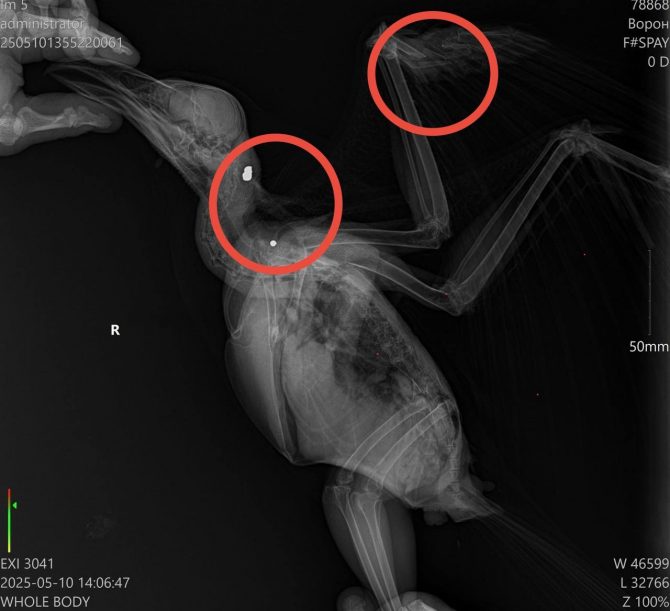

В реабилитационном центре «У Лукоморья» борются за жизнь уникального пациента — ворона с тремя дробовыми ранениями и открытым переломом крыла. Птицу доставили неравнодушные горожане, обнаружившие истекающее кровью создание в городской черте.

«Этот ворон получил три дробины в тело и перелом — результат «забавы» какого-то нелюдя, — с горечью рассказывают волонтеры. — Удивительно, как он вообще выжил после такого».